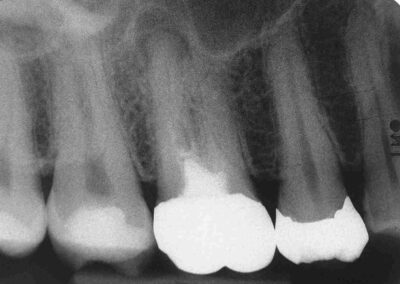

Völlig egal, wie lange das röntgenologisch als apikale Aufhellung dokumentierte „Gleichgewicht des Schreckens“, also die Pattsituation zwischen Angriff der Erreger und Verteidigung durch das Immunsystems an der Wurzelspitze, besteht. Wenn es gelingt, Zugang zu schaffen, gelingt bei indikationsgerechter Behandlung auch die Ausheilung. Und das voraussagbar in einem Prozentsatz von sehr nahe bei 100%. Würde man hier unter Anwendung des aktuell gelehrten Protokolls nach dem sogenannten Goldstandard behandeln, könnten Behandler und Patient allenfalls mit einer Erfolgsquote zwischen nahe bei 60% rechnen.